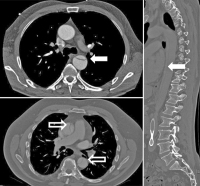

Aortenaneurysma

Abbildung 1: Juxtarenales, teilthrombosiertes abdominelles Aortenaneurysma in axialer (oben links), sagittaler (unten links) und rekonstruierter 3D-Darstellung (rechts, mit fehlender Darstellung des Wandthrombus).

Keywords: abdominelles AortenaneurysmaCT